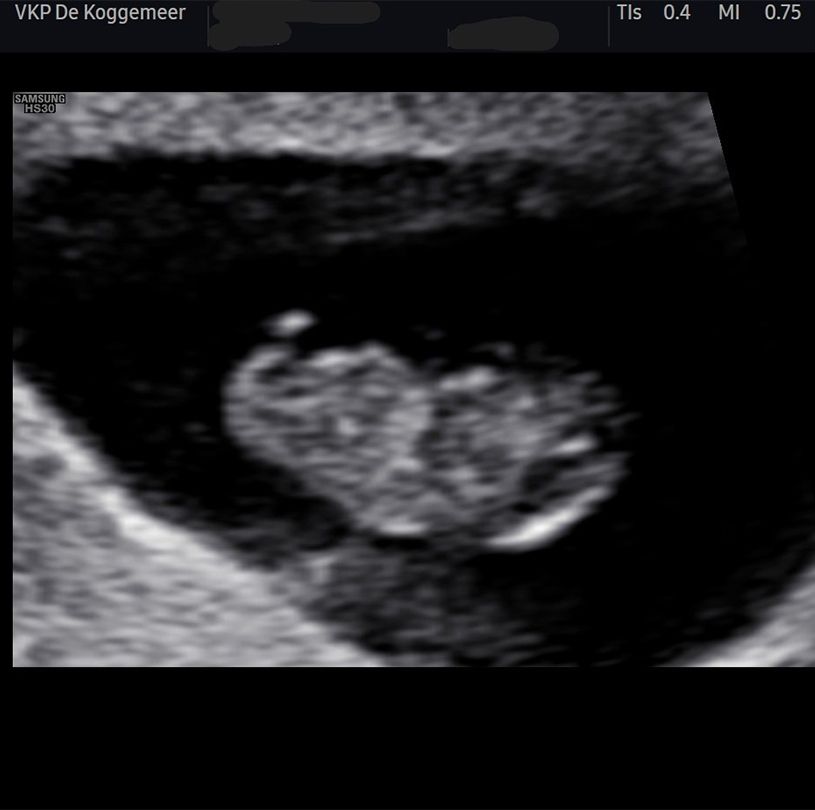

Rond de 8 weken zwangerschap plannen wij de eerste, vroege echo. Dit wordt ook wel een vitaliteitsecho genoemd. Bij deze echo kijken we of de zwangerschap zich in de baarmoeder bevindt, hoeveel weken je ongeveer zwanger bent, of er zich één of meerdere kindjes in de baarmoeder bevinden en of het hartje van de baby klopt.

De vroege echo maken wij meestal zelf op onze locatie in Spierdijk en deze wordt standaard vergoed vanuit de basisverzekering.